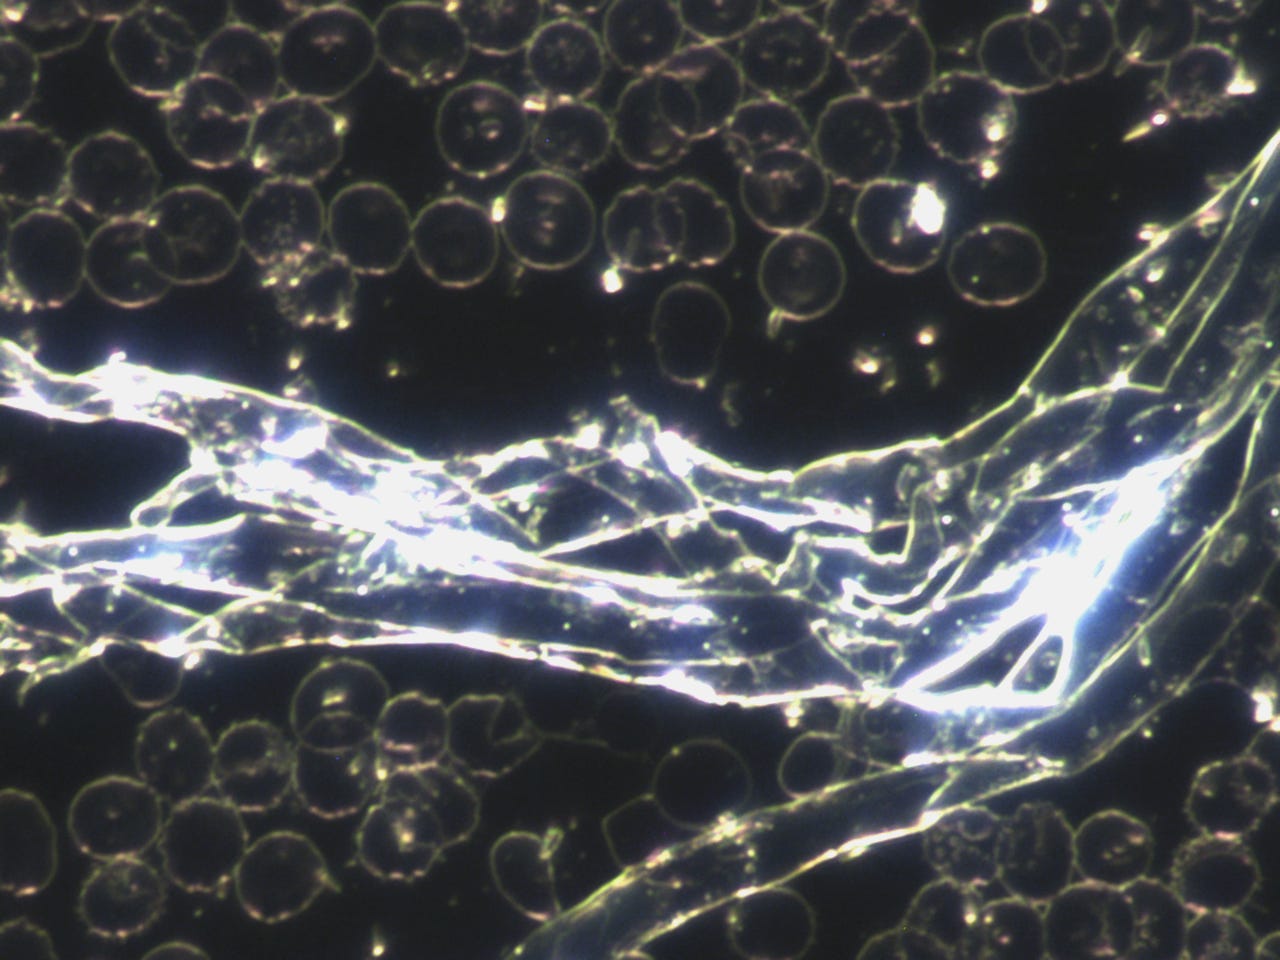

subscribed. Thank you so much. He asked to see my blood before the frequency treatments. The photo’s posted in the previous posts, especially the ones that showed the quantum dots in my blood after the MAH (Major Auto Hemotherapy) with ozone was before the frequency treatments. I am posting them here again, however, I will post some prior to that also.Quantum dots in my blood from Heparin pharmaceutical:

This was the morning after all the quantum dots destroyed my blood:

Anyway here are more before pictures;

I think these really show how messed up my blood was prior to the frequency treatments. I will always be grateful to

, Dr. David Nixon and Clifford Carnicom for their bravery and research to find what was really happening in my blood and all our blood.